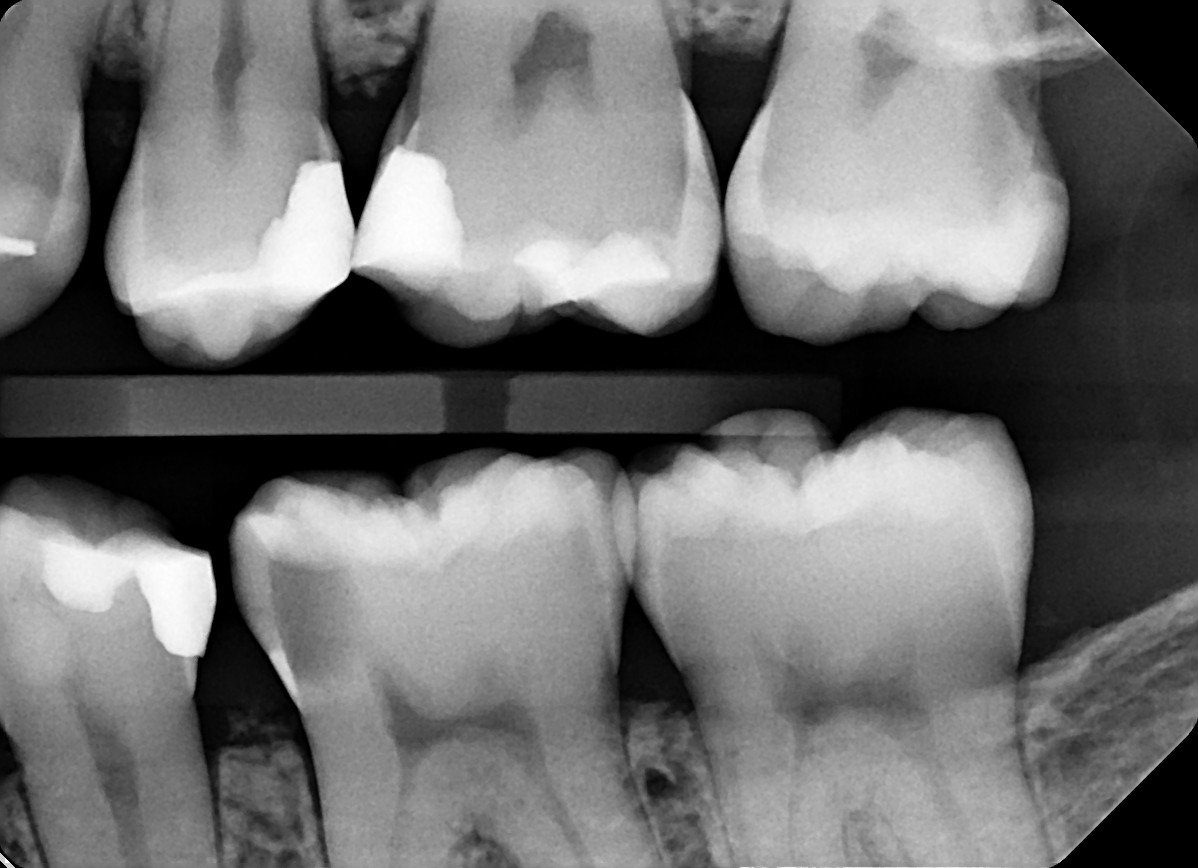

1.  In the X ray bellow for which jaw periodontal bone loss is evident?

2. In the X ray bellow for which jaw periodontal bone loss is evident?